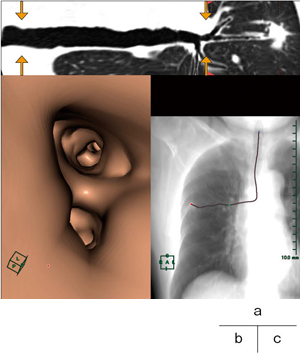

特定した病変内の気管支の断端を始点とし,気管分岐部の上部の終点まで気管支の走行のパスを作成した。CPRでプロットしたパスラインが3D画像上で二次元的に表示されるので,3D画像をレイサム画像(図2)で表示すると,透視下で行うTBLB施行時の鉗子などの位置を把握できる画像(図3)と同じように表現できた。

図2 レイサム画像 |

図3 透視画像 |

図4 CPR

a:ストレッチCPR

b:CPR直交断面

c:レイサム画像

検査施行時,透視画像でしか確認できない現状では,鉗子などを挿入している気管支を正確に判断することが困難であることも多い。透視画像は二次元のデータであり,奥行きの情報を持たない。患者のlateral方向の情報がほしいときには,管球が回転するタイプの透視装置でなければ,気管支鏡を挿入されている患者自身に体位を変えてもらうしかないが,それは大変な困難を伴うことが多い。

CPRでは,作成したパスラインに沿った直交断面を表示することができる。図4 bは,検査に適していると特定した気管支に直交した断面のCT画像である。気管支鏡のシミュレーションを想定して走行を反転して観察すると,気管分岐部から病変まで気管支が分岐していく様子を追うことができる。このとき,パスを引いた気管支は十字でプロットされており,レイサム画像(図4 c)がナビゲーションとなる。しかし,この直交断面は検査医師にとって見慣れない画像であるため,直感的に受け入れられる情報とは言い難い。